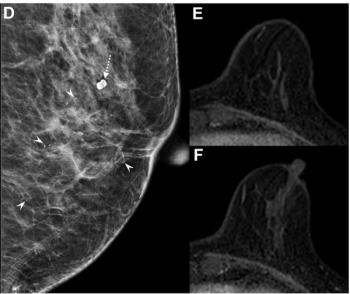

For masses interpreted as BI-RADS category 4 and 5 presentations on breast ultrasound, the authors of a new study found that the presence of echogenic rind had an 81 to 85 percent specificity for malignancy.

Digital breast tomosynthesis (DBT) and synthesized mammography offered a true-positive recall rate of 8.4 per 1,000 women screened vs. 6.2 for digital mammography alone, according to a study involving over 99,000 women.

In light of emerging research suggesting an increased incidence of breast cancer among women under the age of 40, breast radiologists discuss what they’re seeing in practice and emphasize increased vigilance to facilitate early detection.

For HER2-positive breast cancer patients with radiologic complete response on breast MRI after neoadjuvant chemotherapy (NAC), the absence of calcifications was associated with over a 13 percent higher positive predictive value (PPV) for pathologic complete response (pCR).

In a recent interview, Zeeshan Shah, M.D., discussed the challenges of addressing rising breast imaging volume amid the radiologist shortage, the potential of emerging AI solutions for bolstering efficient triage and an increasing incidence of breast cancer presentations in younger patients.

While the AI software offered nearly equivalent negative predictive value (NPV) to radiologist interpretation of digital mammograms and digital breast tomosynthesis (DBT) images, researchers noted that AI had significantly higher recall rates and false-positive results in patients with intermediate risk.